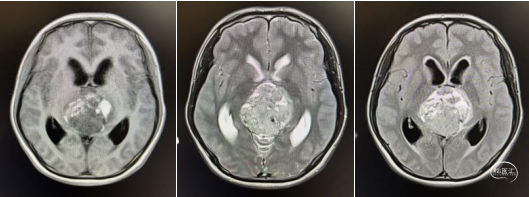

头部MRI显示:松果体区可见一形态不规则肿块,大小约52mm*50mm*51mm,其内信号混杂,呈短-长T1,短-稍长-长T2信号,增强后实质部分可见明显不均匀强化。肿瘤部分突入三脑室内,与三脑室左侧壁及左侧丘脑分界不清,中脑导水管受压变窄,三脑室及侧脑室扩张。右侧脑室前角可见一引流管影。

术前MRI